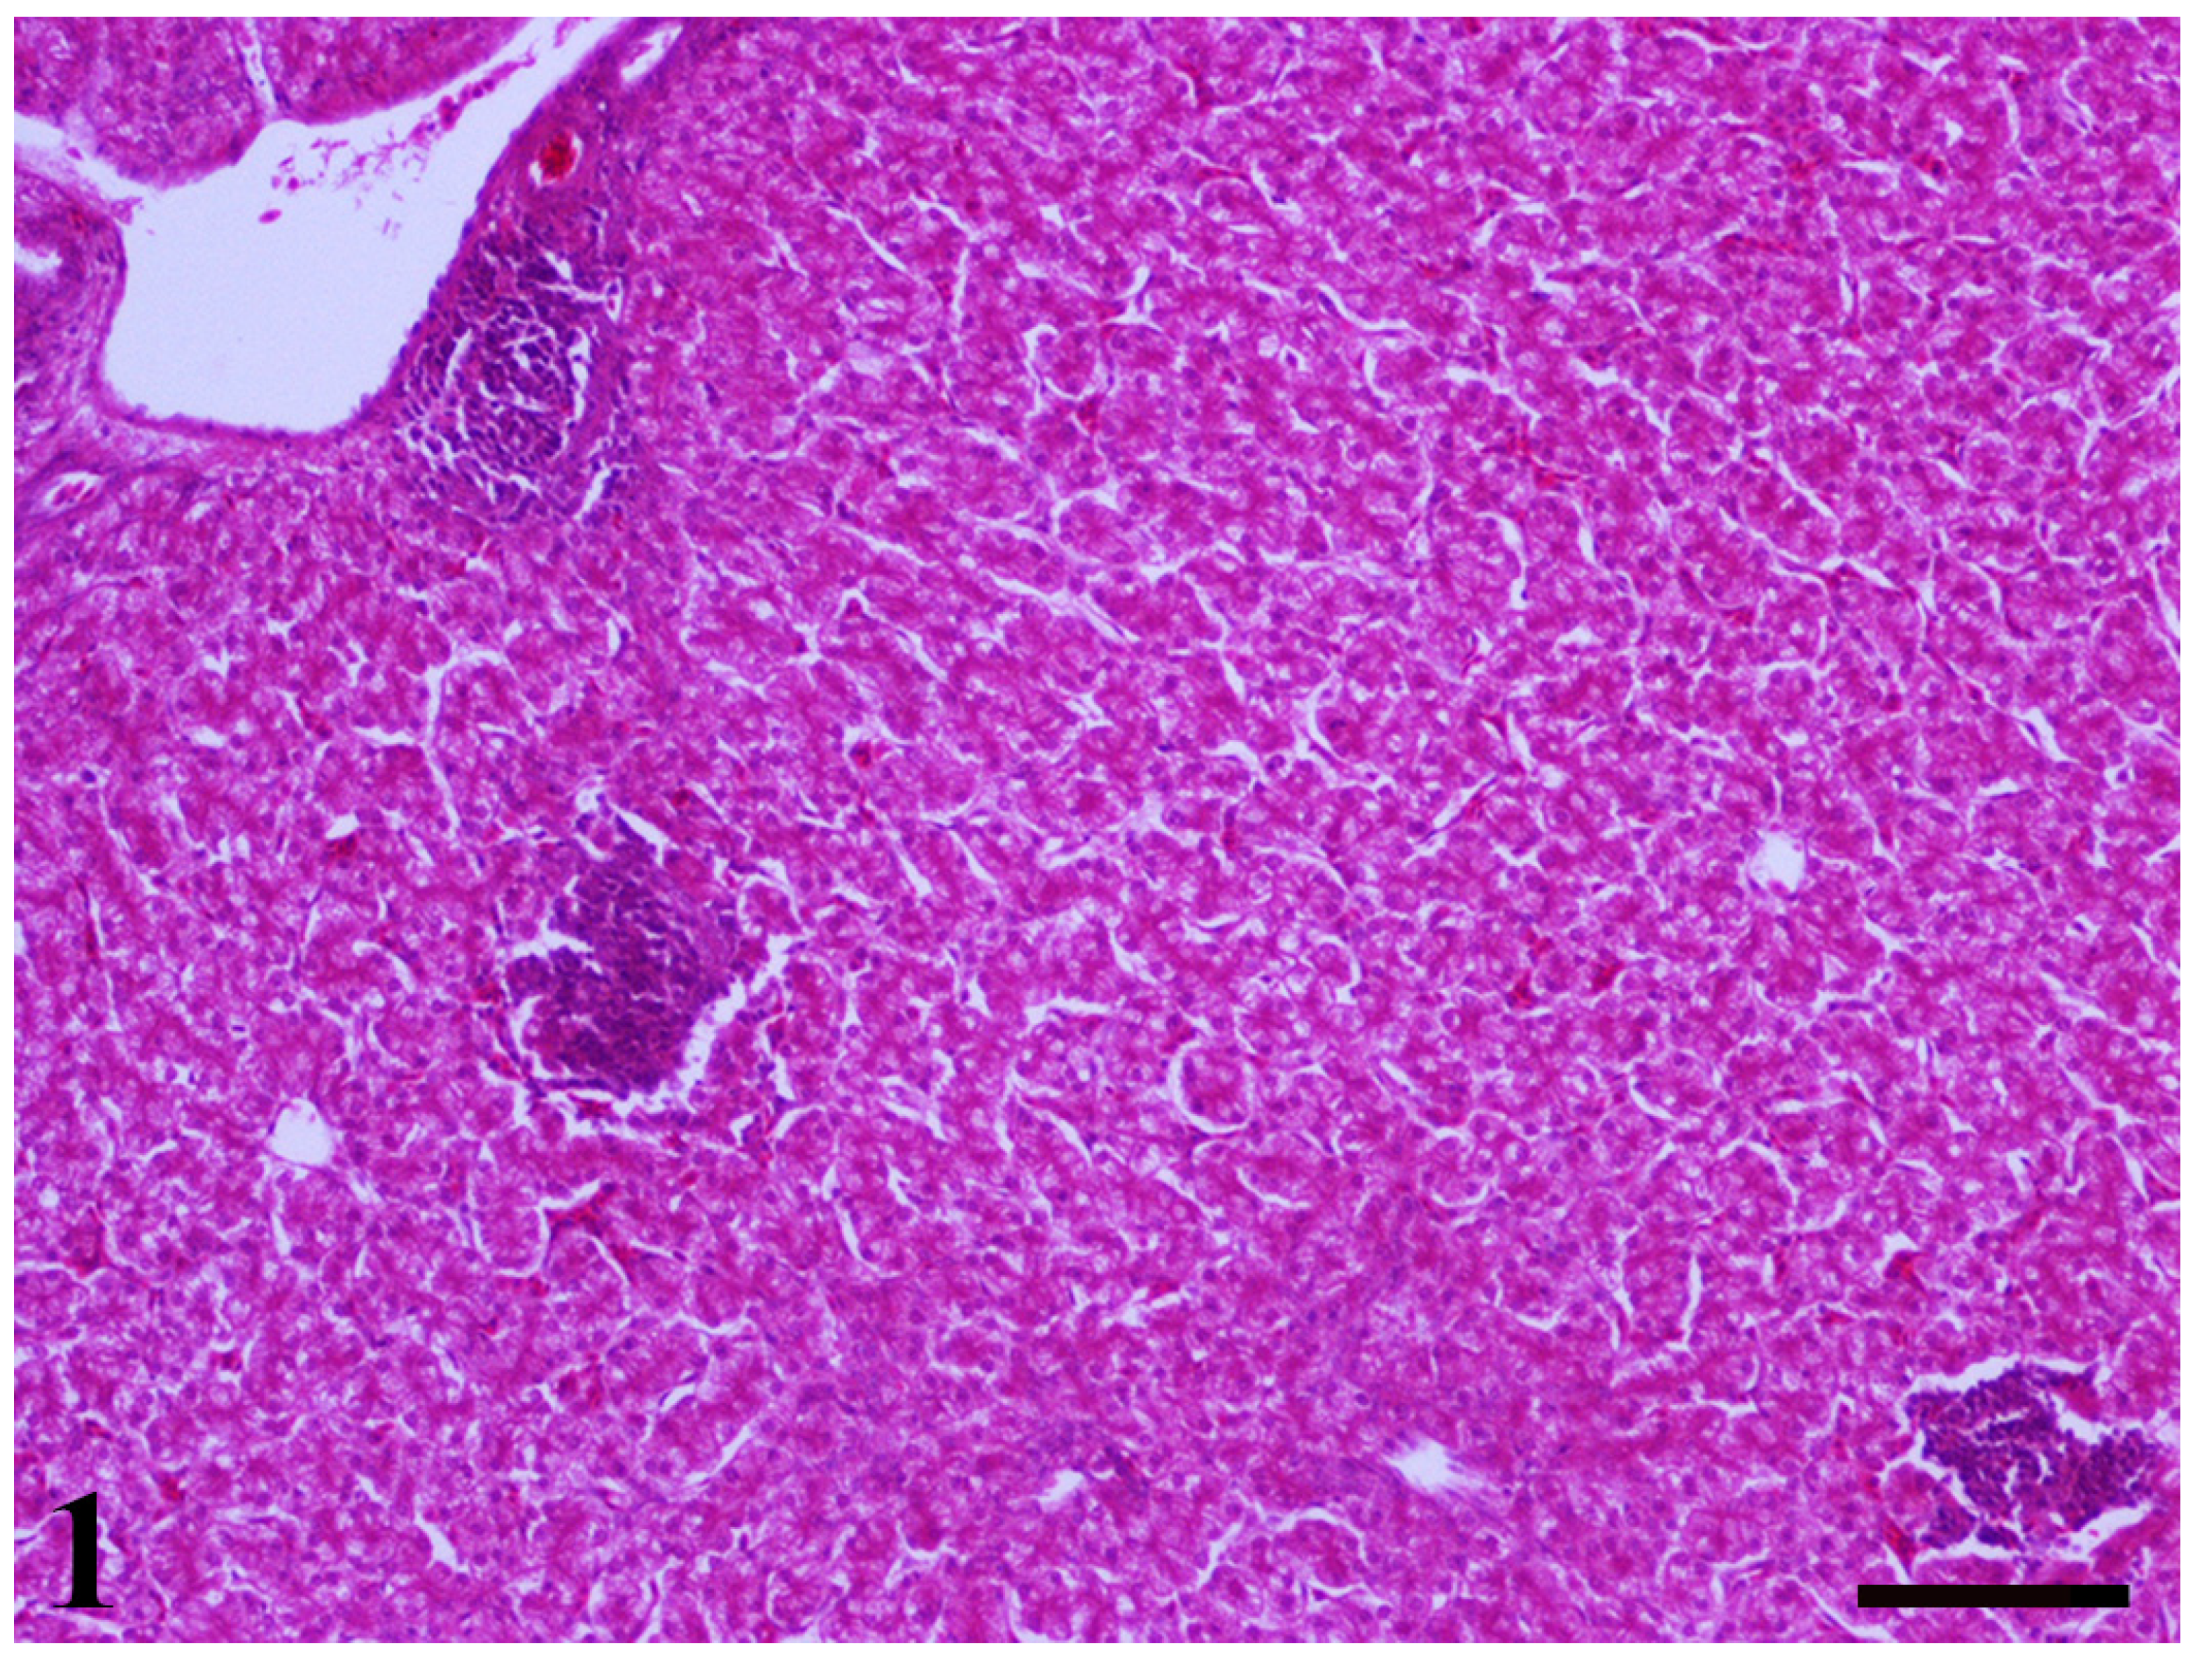

2.5. Histopathological Findings